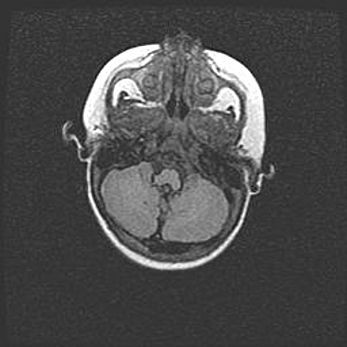

Аномалия Денди-Уокера. Признаки гипоплазии мозолистого тела.

Возраст: 5 месяцев 3 дня

Вес: 5550 г

Пол: мужской

Окружность головы: 39 см

Срок гестации: 40 недель

Аномалия Денди-Уокера – это порок развития головного мозга, для которого характерна триада симптомов: гипотрофия или аплазия червя мозжечка и/или полушарий мозжечка, расширение четвёртого желудочка с формированием ликворной кисты задней черепной ямки, гипертензионная гидроцефалия различной степени.

Гипоплазия мозолистого тела относится к дефектам внутриутробного этапа развития мозговой ткани, возникающим в процессе закладки структур головного мозга, что происходит на начальных этапах развития эмбриона.